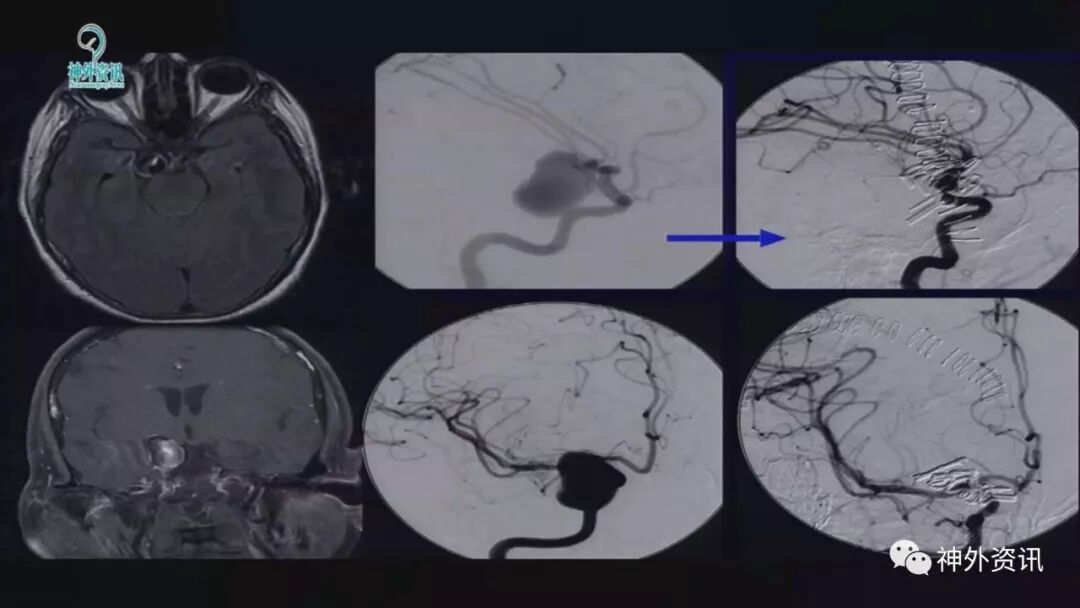

巨大的复杂动脉瘤,常规介入治疗的复发率较高,而目前的血流转向装置也具有治疗后再出血的不确定性。因此,手术治疗仍然在此类疾病中占有重要的地位。但由于相比介入操作而言,手术的难度更大、技术要求更高,也使得许多神经外科医生望而却步。Lawton教授是当今国际上享有盛誉的脑血管病大师,他专注于脑血管病的手术治疗,目前已夹闭各类脑动脉瘤4400余例。除了丰富的临床经验,他非常善于总结,能够将复杂的疾病解剖知识和手术操作要点通俗而又详细的在其著作中表现出来。本期回顾的是Lawton教授所做的关于复杂脑动脉瘤的手术治疗的报告,希望对有志于从事此类挑战性工作的神经外科医师们有所帮助。